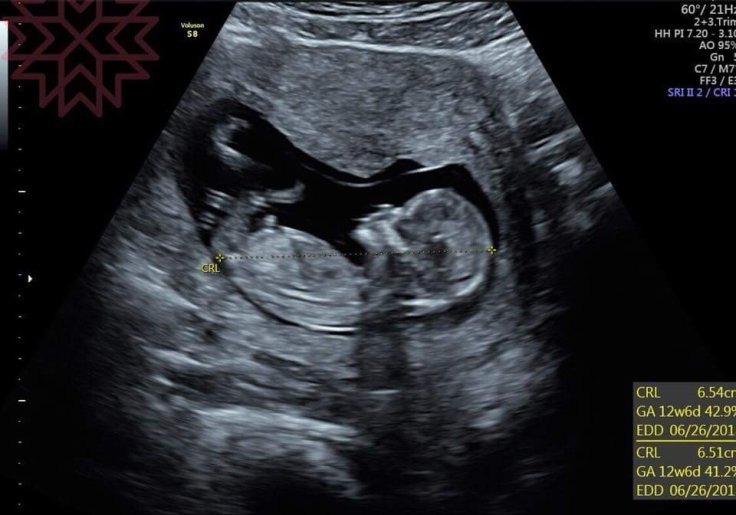

我們利用妊娠12周之前的超音波來測量胎兒的頭臀圍(CRL)

可以很準確地來矯正妊娠週數

也就是可以回推計算出一個符合這樣計算基礎的矯正後最後月經日期

而利用這樣的一個矯正後的日期來當作基準點

對於不論是預產期或是懷孕期間胎兒生長評估的參考性

都是比較合理正確的